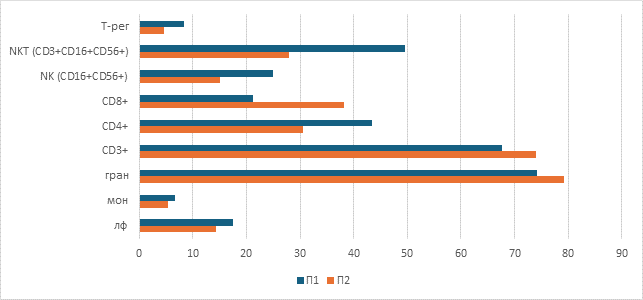

При исследовании чувствительности мононуклеарных клеток периферической крови к берберинуin vitroбыло выявлено стимулирующее влияние берберина на их пролиферативную способность, проявлявшееся увеличением количества и площади формируемых колоний. При этом благоприятный клинический исход ассоциировался не с более высокой базальной колониеобразующей активностью, а с формированием более крупных колоний, что может отражать наличие лимфоцитарных клонов с более высоким пролиферативным и метаболическим потенциалом. Это позволяет предположить, что прогностическое значение может иметь не общее число клеток, а качественные характеристики клонального пролиферативного ответа (рис.3, 4).

Рис.3. Микрофотографии образовавшихся колоний мононуклеарных клеток периферической крови пациента с благоприятным исходом: а – контрольная проба, б – контрольная проба с добавлением ФГА, в – проба с добавлением 1мкмоль/л берберина, г – проба с добавлением 1мкмоль/л берберина и ФГА, д – проба с добавлением 2мкмоль/л берберина, е – проба с добавлением 2мкмоль/л берберина и ФГА, ж – проба с добавлением 4мкмоль/л берберина, з – проба с добавлением 4мкмоль/л берберина и ФГА.

Примечание: составлен авторами по результатам данного исследования

У пациента с благоприятным клиническим ответом изначально отмечалась более низкая базальная колониеобразующая активность МНПК: количество колоний было на 56% меньше по сравнению с пациентом с рефрактерным течением заболевания, однако их средняя площадь превышала данный показатель на 22%. Воздействие берберина в исследованных концентрациях вызывало дозозависимое усиление колониеобразующей способности МНПК у обоих пациентов, при этом наибольшая стимуляция наблюдалась при сочетанном применении берберина и фитогемагглютинина, что свидетельствует о синергическом эффекте изучаемого соединения с митогенной стимуляцией (рис.5, 6). Использование ФГА позволило оценить влияние берберина в условиях активированной иммунной реакции, что приближаетмодель in vitro к условиям реализации противоопухолевого иммунного ответаin vivo.

Кроме того, были выявлены индивидуальные различия в чувствительности МНПК к берберину: у пациента с полным ответом на терапию наибольшее увеличение количества колоний наблюдалось при концентрации 1мкмоль/л, тогда как у пациента с неблагоприятным исходом пик пролиферативного ответа смещался на 2мкмоль/л (рис.5). Полученные различия могут объясняться особенностями метаболической и пролиферативной активности отдельных лимфоцитарных клонов. Более крупные колонии у пациента с благоприятным исходом могут отражать наличие клонов с высоким метаболическим потенциалом и способностью к интенсивному клеточному делению, тогда как большее число, но мелких колоний у пациента с неблагоприятным исходом может соответствовать функционально менее активным клональным линиям.